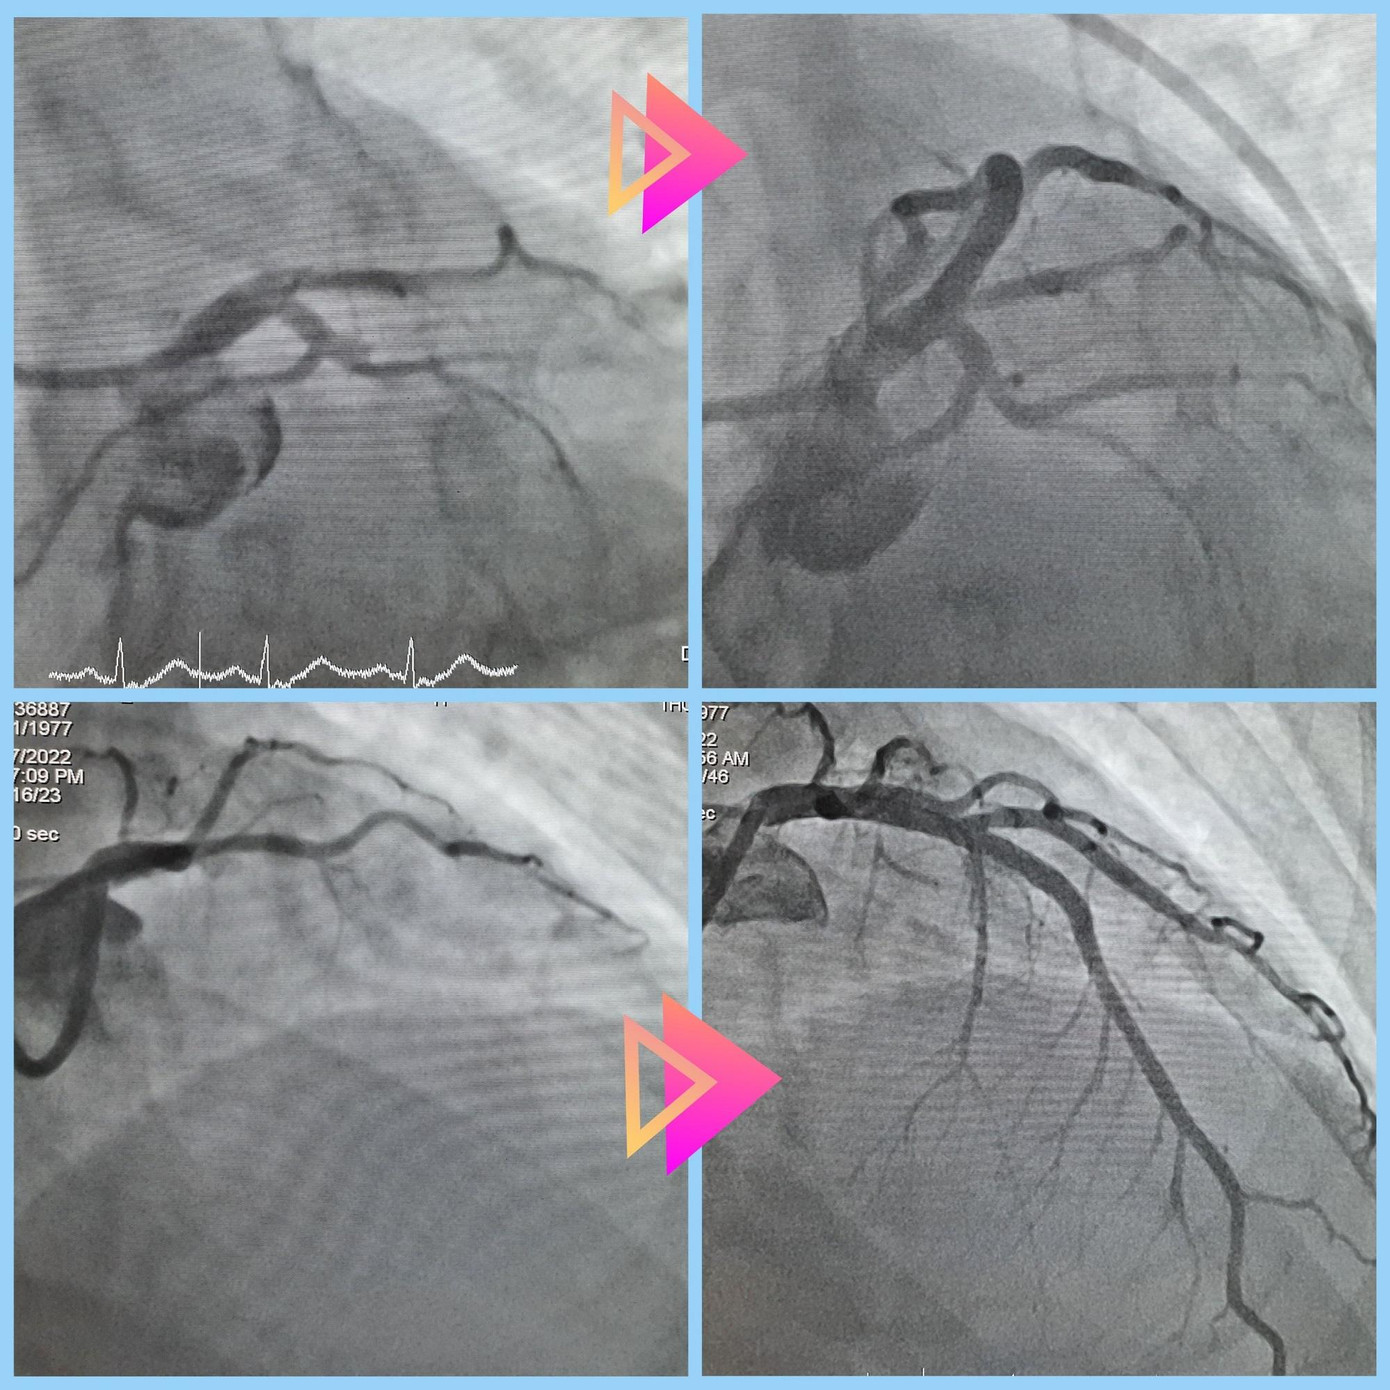

Qua chẩn đoán hình ảnh, bác sĩ xác định người bệnh bị nhồi máu cơ tim cấp, nguy cơ tử vong bất kỳ lúc nào. Sau hội chẩn nhanh liên chuyên khoa, các bác sĩ đã quyết định thực hiện thông tim can thiệp khẩn nhằm tái thông mạch vành cho người bệnh.

BS Nguyễn Thái Anh, khoa Hồi sức Tim mạch cho biết, trong quá trình can thiệp, ê kíp ghi nhận người bệnh bị tắc hoàn toàn nhánh động mạch vành liên thất trước. Bằng thiết bị chuyên dụng, các bác sĩ đã hút huyết khối, đặt stent tại vị trí tắc mạch, tái thông thành công dòng chảy mạch vành.

| Mạch máu của bệnh nhân trước (hình trên) và sau can thiệp (hình dưới) nhồi máu cơ tim cấp |

Các bác sĩ đánh giá đây là trường hợp tiểu cầu tăng rất cao 820 G/L (bình thường dưới 400 G/L). Bệnh nhân thuộc nhóm nguy cơ cao và có khả năng tái thành lập huyết khối sau can thiệp. Trước nguy cơ trên, bệnh viện đã phối hợp thuốc giảm tế bào (Hydroxyurea) song song với kháng đông và kháng kết tập tiểu cầu. Sau 10 ngày nằm viện theo dõi, bệnh nhân hết đau ngực, sức khỏe đang bình phục tốt.